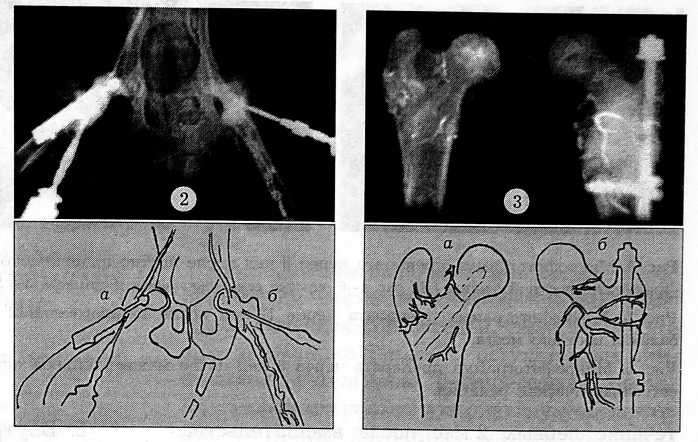

Внутрикостная флебография, выполнявшаяся во все сроки наблюдения, показала, что после костной аутопластики в 60% случаев развивается компенсаторный механизм оттока контрастного вещества из аваскулярной головки в виде диафизарного рефлюкса. При межвертельной остеотомии такого механизма нет, поскольку в момент операции пересекаются все внутрикостные сосуды (рис. 2). Задержка эвакуации контрастного вещества из проксимального отдела бедренной кости после операции типа Э.И. Шаиро отмечалась в 63% случаев и во всех случаях — после межвертельной остеотомии. Это свидетельствует о наличии стойкой гиперемии в зоне остеотомии.

Рис. 2. Внутрикостная контрастная флебограмма через 12 нед после межвертельной остеотомии (а) и костной аутопластики трансплантатом на мышечной ножке (б). Рис. 3. Рентгенограммы проксимального отдела бедренных костей через 12 нед после костной аутопластики трансплантатом на мышечной ножке (а) и межвертельной остеотомии (б).